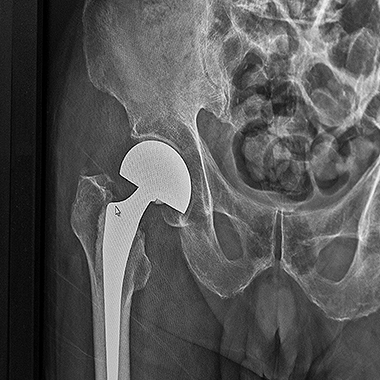

Endoproteza stawu biodrowego

Jest to jeden z najbardziej zaawansowanych i precyzyjnych sposobów operacyjnego leczenia biodra, który pozwala na przeprowadzenie zabiegu bez przecinania mięśni, przez naturalne przestrzenie anatomiczne. Technika ta zyskuje coraz większe uznanie w leczeniu choroby zwyrodnieniowej stawu biodro wego, szczególnie wśród pacjentów poszukujących szybszego powrotu do aktywności.

Zabieg wykonuję z użyciem wysokiej jakości, nowoczesnych implantów dobieranych indywidualnie do budowy anatomicznej i potrzeb pacjenta. Całość leczenia opiera się na zasadach tzw. szybkiej ścieżki (fast-track), co oznacza także odpowiednio zaplanowaną rehabilitację i stały nadzór pooperacyjny. Dzięki takiemu podejściu, endoprotezoplastyka biodra w moim wykonaniu stanowi skuteczną i bezpieczną metodę leczenia zwyrodnienia stawu biodrowego – szczególnie dla pacjentów oczekujących szybkiego powrotu do sprawności.